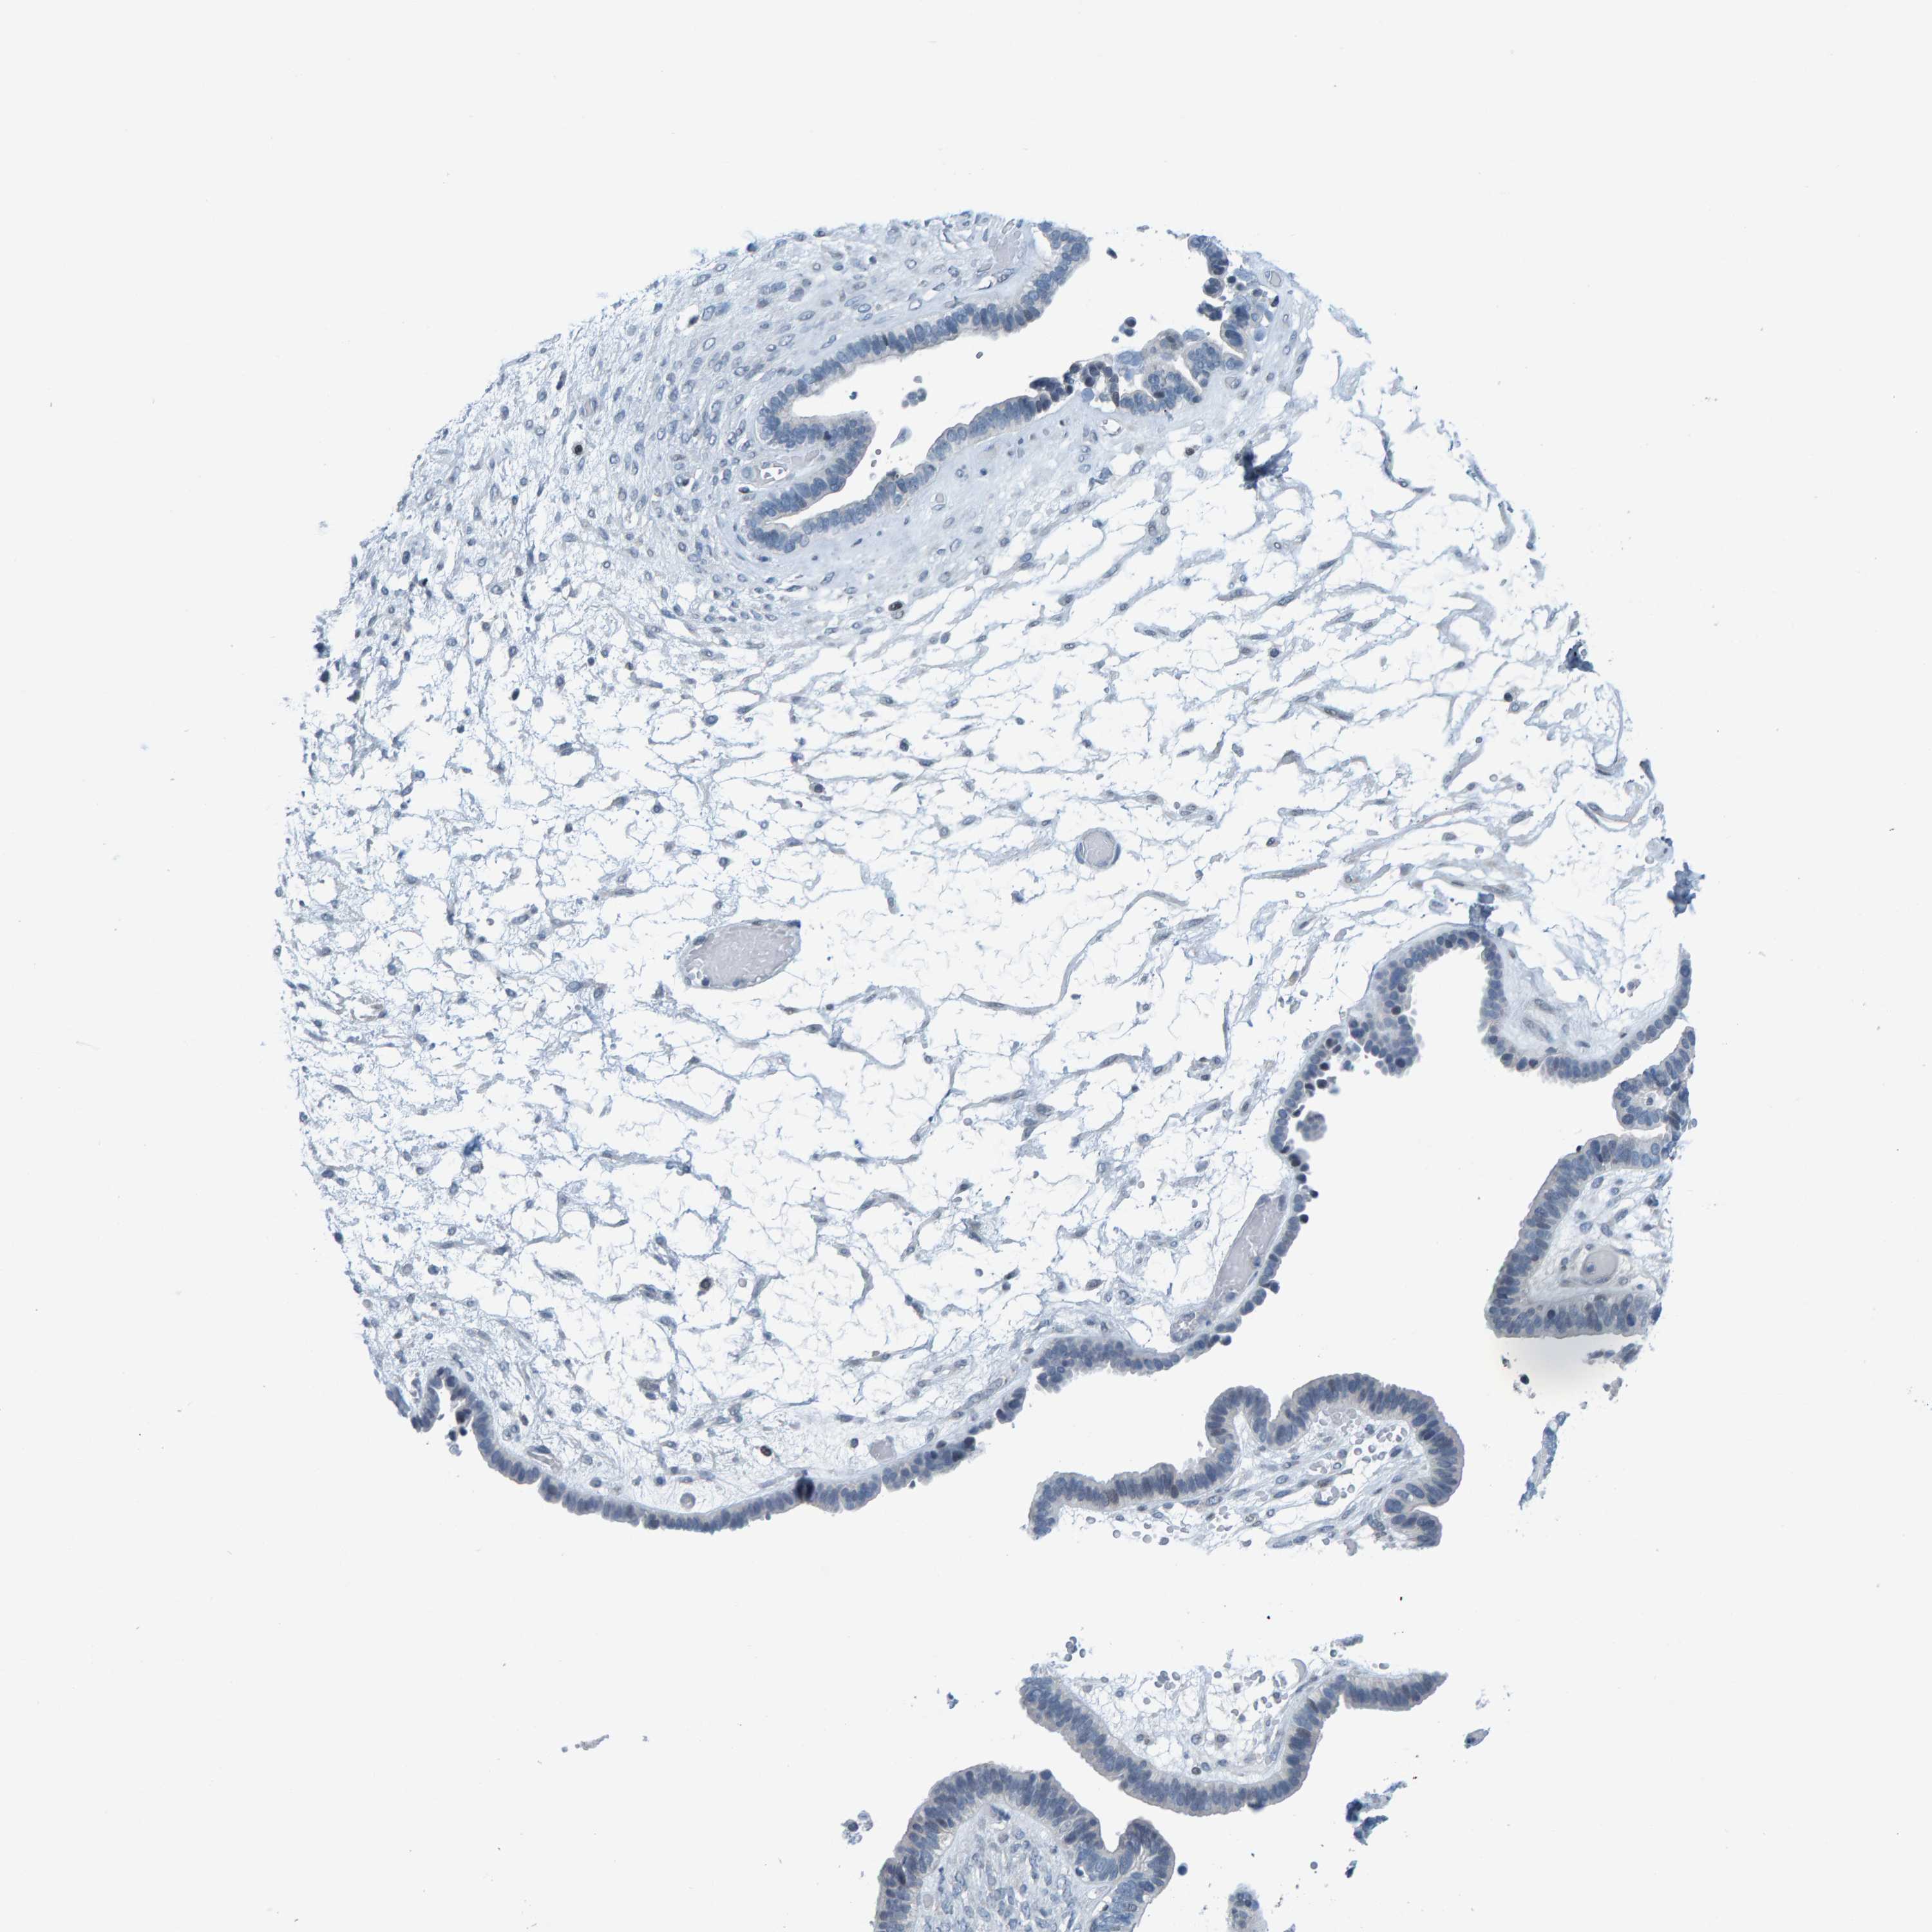

OVARIAN CANCER - Protein expressioni

A mouse-over function shows sample information and annotation data. Click on an image to view it in a full screen mode. Samples can be filtered based on level of antibody staining by selecting one or several of the following categories: high, medium, low and not detected. The assay and annotation is described here.

Note that samples used for immunohistochemistry by the Human Protein Atlas do not correspond to samples in the TCGA dataset.

Antibody stainingi

Antibody staining in the annotated cell types in the current human tissue is reported as not detected, low, medium, or high, based on conventional immunohistochemistry profiling in selected tissues. This score is based on the combination of the staining intensity and fraction of stained cells.

Each image is clickable and will lead to virtual microscopy that enables deeper exploration of all samples and also displays staining intensity scores, fraction scores and subcellular localization as well as patient and tissue information for each sample.

Cystadenocarcinoma, serous, NOS

Carcinoma, endometroid

Cystadenocarcinoma, mucinous, NOS

Carcinoma, NOS